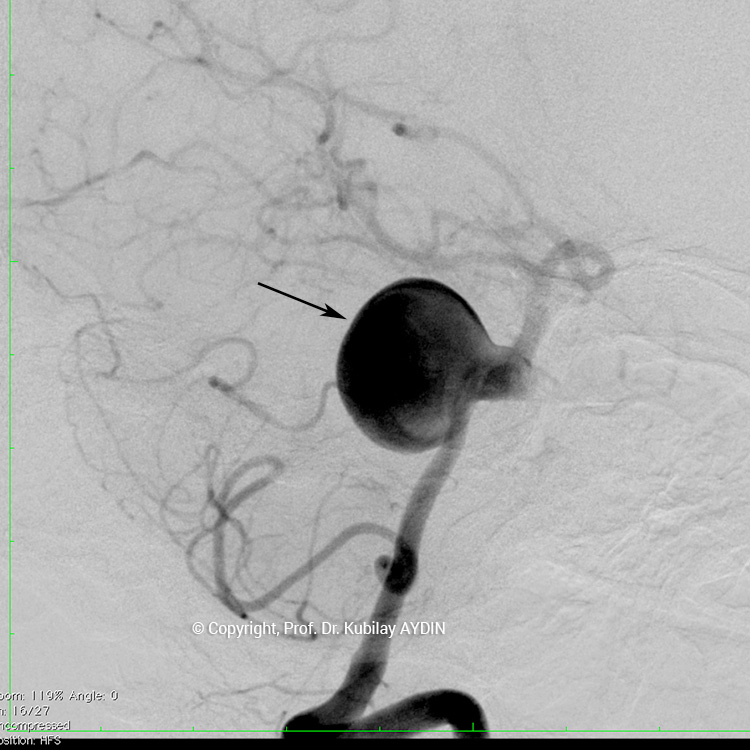

Anevrizma kesesinin damarla birliştiği noktasına, “anevrizmanın boynu” denir. Boynu geniş olan anevrizmaların tedavisinde, anevrizma içine konulacak koillerin, anadamar içine sarkmaması için yardımcı cihazlar kullanmak gerekebilir. Geniş boyunlu anevrizmaların koillenmesi sırasında özel yapıda balonlar veya stentler (metal kafes) kullanmak gerekebilir.

Geniş boyunlu anevrizmaların stent kullanılarak koillerle kapatılması işlemine “stent-yardımlı koilleme” adını veriyoruz. Bu işlemin ilk aşamasında anevrizmanın boynunu örtecek şekilde damar içine bir metal kafes (stent) yerleştirilerek, bir sonraki aşamada anevrizma kesesi içine konulan koillerin damar içine sarkması önlenir. Yani, burada stentin görevi, anevrizma içine doldurduğumuz koil adı verilen tellerin, damar içine sarkmasını önlemektir. Stent-yardımlı koilleme, geniş boyunlu anevrizmaların kapalı yöntemle tedavisinde tercih edilen bir yöntemdir.

Stent yardımlı koilleme tekniği ile anevrizma tedavisinde, anevrizmanın yerleştiği atardamar içerisine stent açılması için bir kateter yerleştirilir. Eş zamanlı olarak, anevrizma kesesi içerisine koilleme amaçlı farklı bir kateter yerleştilir. Damar içerisine bir stent açıldıktan sonra, anevrizma içerisideki kateterden gönderilen platinden yapılmış çok yumuşak yapıda koillerle anevrizma kesesi doldurulur. Stent, anevrizma içeriside bırakılan koillerin damar içine sarkmasına engel olur. Koilleme işlemine, anevrizma koillerle tamamen doldurulana ve anevrizma içine kan girmeyene kadar devam edilir.